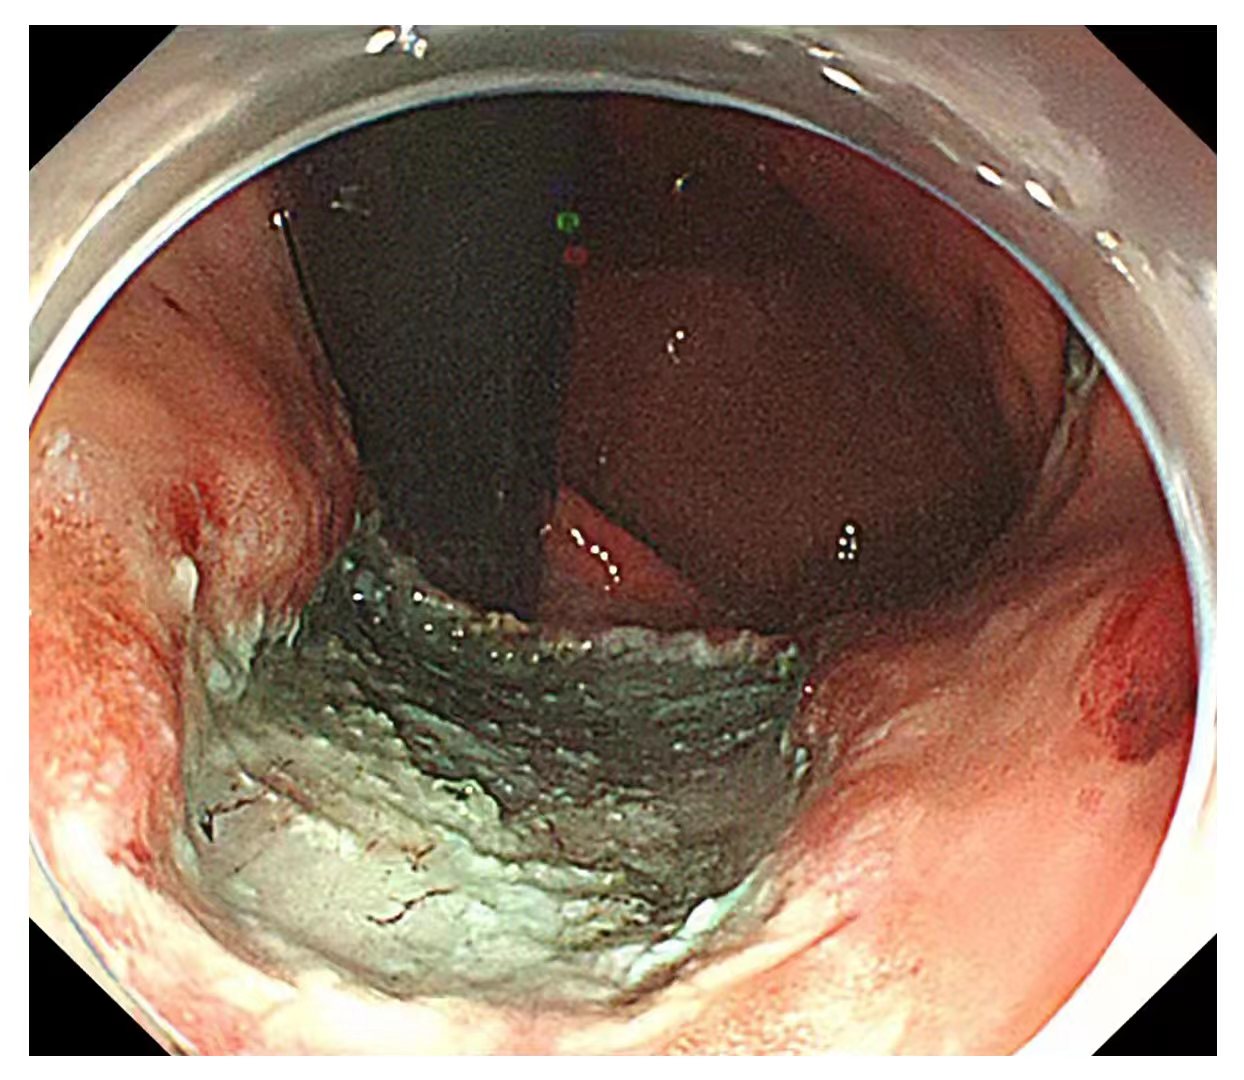

内镜中心独立完成了多例食管、胃、结肠早癌完整切除术,并成功开展了食管良性狭窄切开术,间质瘤挖除术,食管癌伴食管狭窄支架置入术,消化道异物取出术,痔疮Ⅱ度以内的硬化术等。